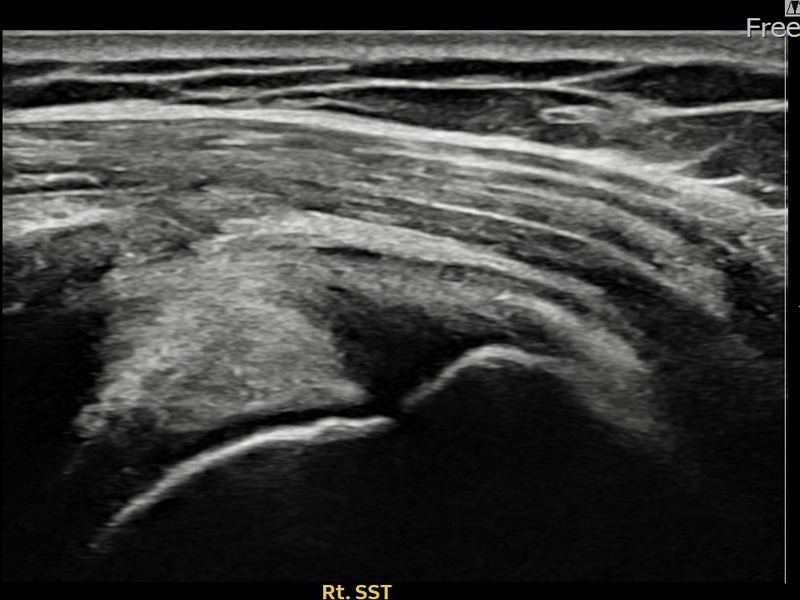

최ㅇㅇ님 · 우측 극상근건 관절면측 파열 진행형

우측 어깨 파열이 진행된 상태로 수술 없이 치료를 원해 내원하셨습니다. 다각도 초음파 평가 후 축소봉합술을 시행하여 힘줄 구조가 안정화되었습니다.

상세 보기 →